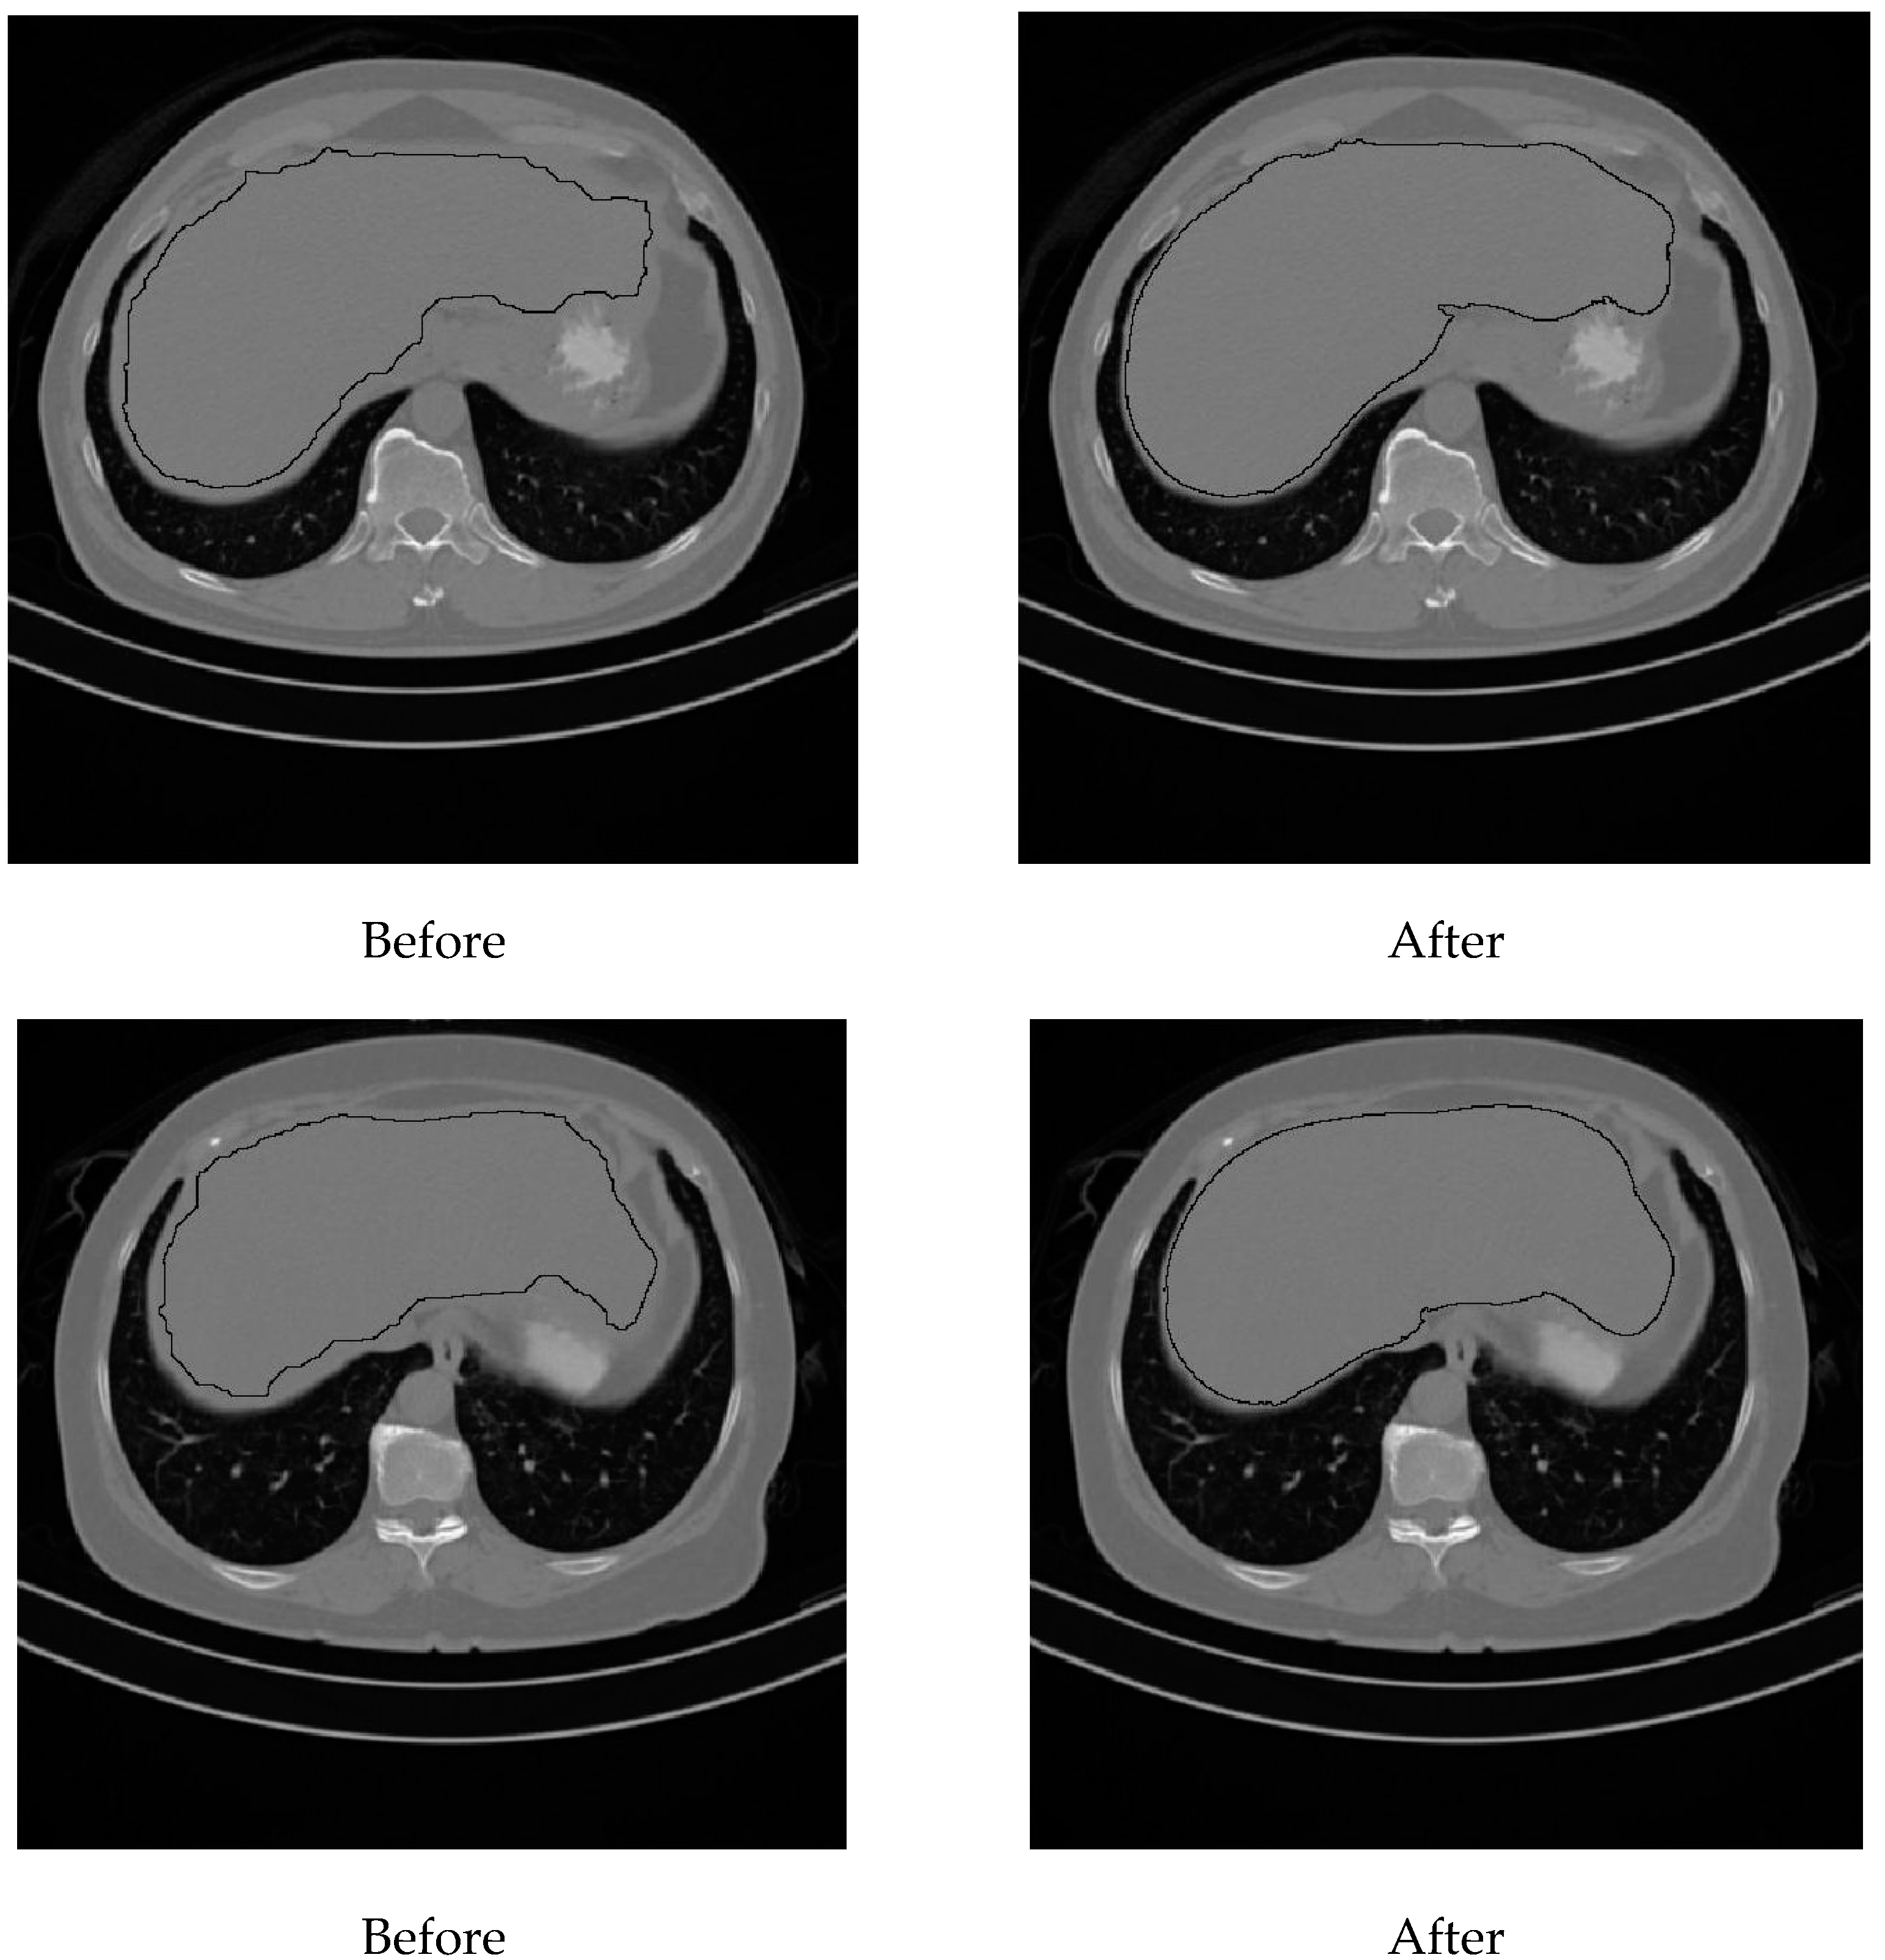

Figure 6 shows the result of segmenting the liver in Iss for two subjects. To the left, the initial segmentation results are shown, and to the right, the results of applying the proposed enhancement method are shown.

Figure 6. Final liver segmentation in the starting slices.